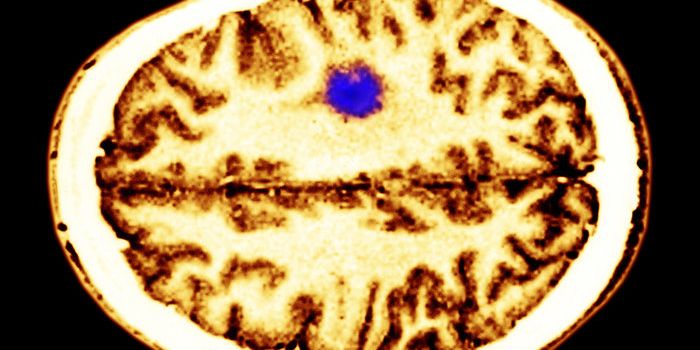

MAY 04, 2016NeuroscienceRupture of small blood vessels in the brain can cause hemorrhagic stroke and brain microbleeds, and finding the fastest ...